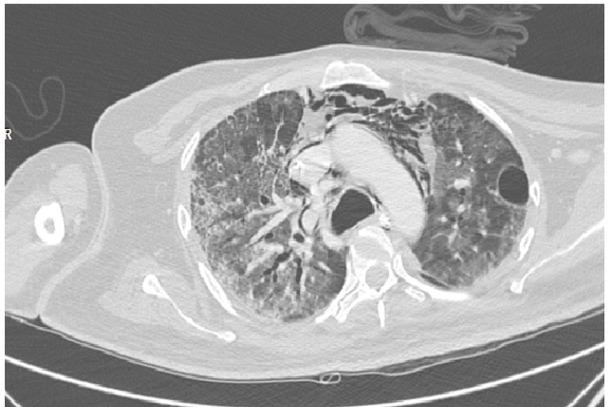

Fig. 1B